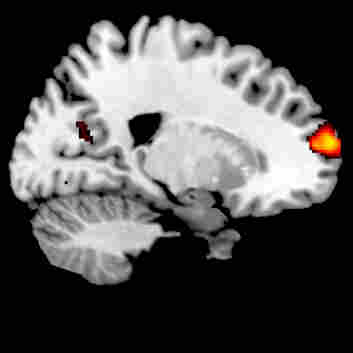

To better understand how gamers acquire these non-gaming skills, neuroscientist Lauren Sergio, of York University in Toronto, looks inside the brain. She's found an important difference between gamers and non-gamers in how and where the brain processes information. She likens skilled gamers to musicians.

Skilled gamers mainly use their frontal cortex, according to Sergio's fMRI studies. That's an area of the brain specialized for planning, attention and multitasking. Non-gamers, in contrast, predominately use an area called the parietal cortex, the part of the brain specializing in visual spatial functions.

"The non-gamers had to think a lot more and use a lot more of the workhorse parts of their brains for eye-hand coordination," Sergio says. "Whereas the gamers really didn't have to use that much brain at all, and they just used these higher cognitive centers to do it."